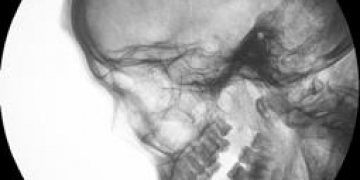

Divuit mòmies de procedència desconeguda varen aparèixer sota la llum de les llanternes després de dècades d’anonimat. Calia fer-les reviure, descobrir el seu passat i desvetllar la incògnita del seu origen.

Podrien procedir aquestes mòmies de la tomba de Monthemhat? Quan i per què van ser traslladades? Un equip format per egiptòlegs, arqueòlegs, antropòlegs, metges paleopatòlegs i radiòlegs, van rescatar de l’oblit aquests antics personatges i van descobrir tot el possible al voltant de la seva vida i mort, gràcies als diversos estudis i analítiques realitzades.

Projecte Monthemhat. Les mòmies oblidades presenta per primera vegada els rostres d’aquestes mòmies, magníficament conservats, a través d’un recorregut fotogràfic que analitza les malalties que hi patiren en vida, endinsant-se, alhora, en el fascinant món de la momificació i d’aquest complex ritual pel qual els antics egipcis tractaren de vèncer la mort.

Mòmia